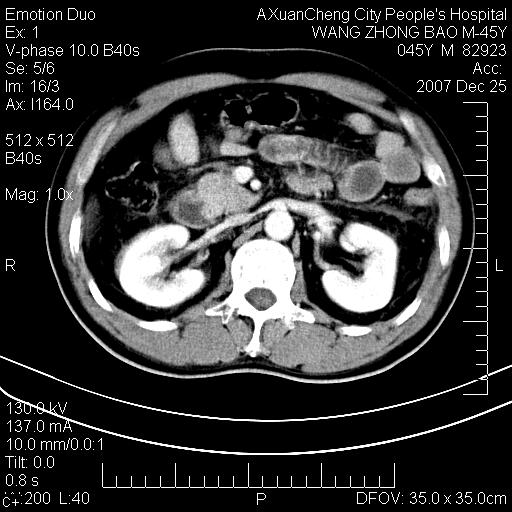

以下是引用qiuleiyu在2007-12-25 18:14:00的发言:[br]胰腺增大,周边渗出改变,肾前筋膜明显增厚,示少量积液.胆囊壁毛糙,周边少许渗出,胆总管壁厚,异常强化,然扩张不明显.结合病程急短;考虑;胆管炎,胆囊炎,胆源性胰腺炎可能大,请结合实验室检查及随访.

以下是引用lisihao在2007-12-25 14:23:00的发言:[br]急性水肿型胰腺炎[br]依据:1、胰腺弥漫性肿大,边缘稍毛糙;[br] 2、双侧肾周筋膜增厚,尤以左侧为甚(重要征象)[br] 3、双侧后胸膜增厚(刺激性炎症);[br] 4、结合病史,查血尿淀粉酶应该可以确诊。